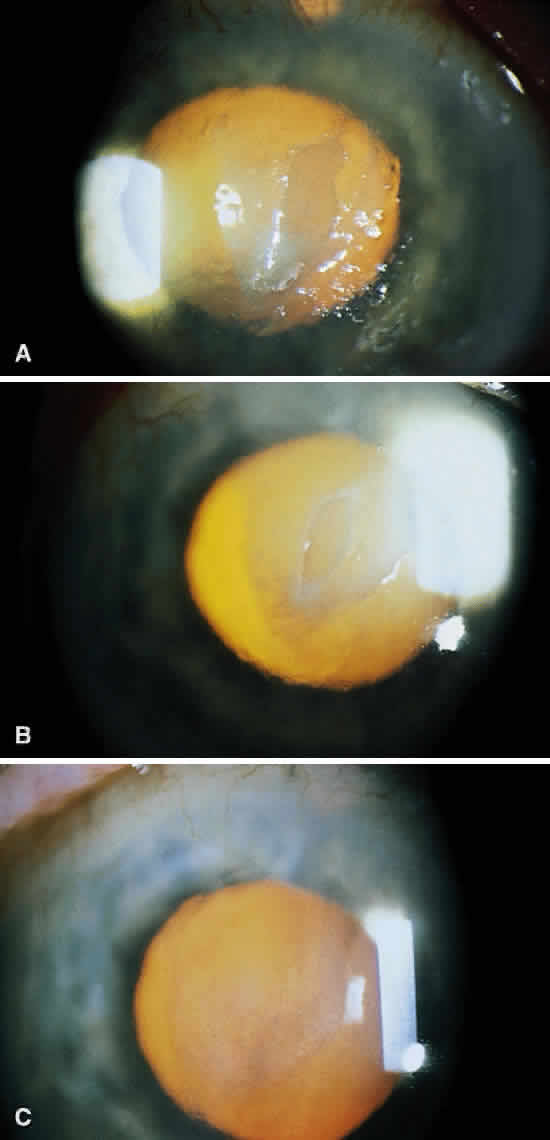

Corneal ulcers caused by S. pneumoniae are typically described as serpiginous or creeping and most often spread toward the center of the cornea. They are characterized by a gray-yellow disc-shaped ulcer with an overhanging margin at the advancing edge (Fig. 5). The ulcer usually progresses rapidly, extending into the deep stroma and often leading to corneal perforation. Extensive damage to corneal tissue, as well as a characteristic sterile hypopyon, are caused by the rapid production of bacterial exotoxin within the stroma.40,41

Streptococcus viridans (alpha streptococcus), although of low-grade pathogenicity, may be a cause of corneal ulceration, particularly in the locally immunosuppressed host.42 The organism produces a characteristically indolent, anterior stromal inflammatory reaction that is slow to progress and that may be accompanied by a minimal to moderate anterior chamber reaction. The ulcer is usually well circumscribed, gray-white, “dry” in appearance, and lying beneath a well-demarcated epithelial defect (Fig. 6). Because the organism is of relatively low-grade pathogenicity, the infection responds rapidly to specific antibiotic therapy.